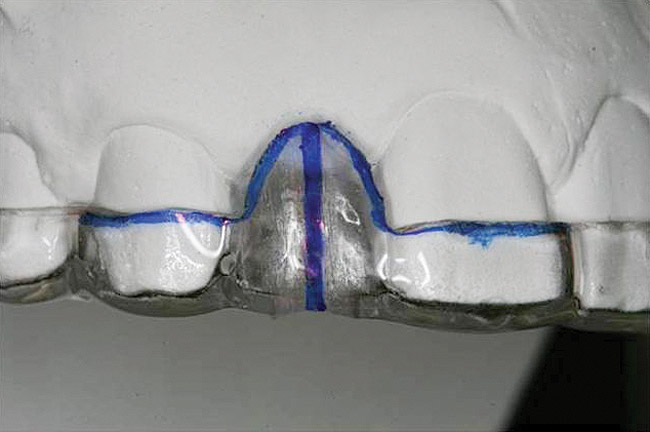

Figure 13   Exploiting study casts for planning single-tooth implant placement and restoration: Mounted study casts permit an estimation of available bone volume (Fig 13); measure the bound edentulous space inter-tooth dimensions (Fig 14); measure the available inter-arch dimension (restorative space) (Fig 15); and evaluate alveolar ridge/tooth relationships (distance from zenith represented by plastic stent to ridge crest) (Fig 16).

Figure 14   Exploiting study casts for planning single-tooth implant placement and restoration: Mounted study casts permit an estimation of available bone volume (Fig 13); measure the bound edentulous space inter-tooth dimensions (Fig 14); measure the available inter-arch dimension (restorative space) (Fig 15); and evaluate alveolar ridge/tooth relationships (distance from zenith represented by plastic stent to ridge crest) (Fig 16).

Figure 15  Exploiting study casts for planning single-tooth implant placement and restoration: Mounted study casts permit an estimation of available bone volume (Fig 13); measure the bound edentulous space inter-tooth dimensions (Fig 14); measure the available inter-arch dimension (restorative space) (Fig 15); and evaluate alveolar ridge/tooth relationships (distance from zenith represented by plastic stent to ridge crest) (Fig 16).

Figure 16  Exploiting study casts for planning single-tooth implant placement and restoration: Mounted study casts permit an estimation of available bone volume (Fig 13); measure the bound edentulous space inter-tooth dimensions (Fig 14); measure the available inter-arch dimension (restorative space) (Fig 15); and evaluate alveolar ridge/tooth relationships (distance from zenith represented by plastic stent to ridge crest) (Fig 16).